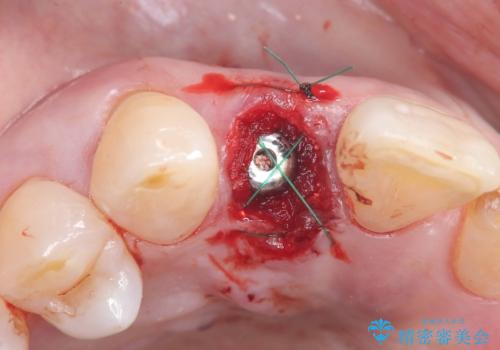

インプラント治療は、低侵襲で短期間に行える「抜歯即時インプラント治療」を選択しました。

この方法は、抜歯したその日にインプラントを埋入し、手術が1回で済むのが大きな特徴です。

治療期間も短く、抜歯からわずか3か月でオールセラミッククラウンを装着することができます。

また、オペ当日には仮歯まで装着するため、見た目を気にせず普段通りの生活を送ることができます。